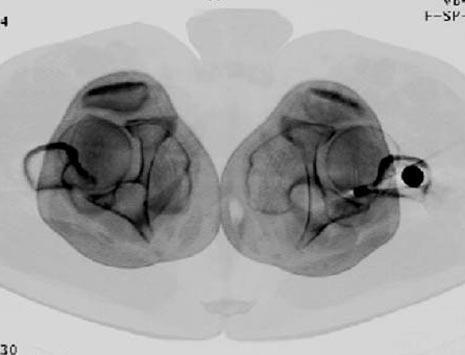

Снимки представлены: 1 мес; 3 мес; 1 год; 2 года, предоперационные и ротационная КТ грамма

Деформация:

Вальгус- 17 градусов

Рекурватум 5 градусов

Укорочение 2.5см

Ротационно 22 градусов внутренная

Смещение диафиза по поперечнику 75%